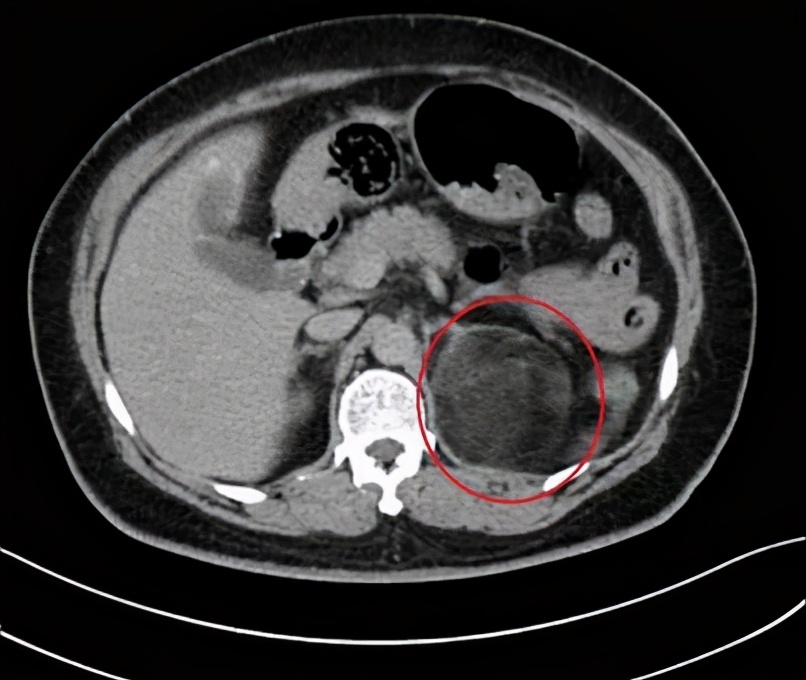

贵航三〇〇医院泌尿科主任李永光说,患者丁女士,住院前是比较肥胖,而且这个肥胖已是好多年了,通过查体发现左侧肾上腺长了一个巨大的肿瘤。初步判断这个肿瘤是造成她肥胖和血压高的罪魁祸首。

尤其是最近这段时间,丁女士的血压一直是居高不下,这让她意识到问题的严重,不得不住院治疗。医生一检查,丁女士肾上腺的肿瘤已经长到8了厘米,已经严重影响压迫肾脏,需要进行手术摘除。

经过一个星期的精心准备,2月26号,医生对丁女士实施了手术,从丁女士肾上腺上摘除了8厘米大的肿瘤。